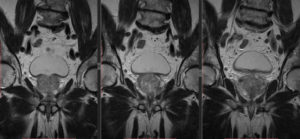

МРТ позволяет рассмотреть различные структуры мягких тканей со всех ракурсов. Сканирование происходит в нескольких плоскостях (проекциях):

- Аксиальная (поперечная, Ax) – показывает поперечные срезы органа (параллельно пяткам).

- Сагиттальная (продольная, Cag) – делит орган на левую и правую часть, это срез сбоку.

- Коронарная (фронтальная, Cor) – проходит вдоль передне-задней оси, перпендикулярно саггитальной. Исследуемая область при этом делится на заднюю и переднюю части.

Для каждого органа наиболее информативна одна из вышеперечисленных проекций, а остальные уточняют изображение. Для простаты важны сагиттальная и аксиальная плоскости. При исследовании визуализируются следующие области:

МР-анатомия простаты (с эндоректальным датчиком)МРТ простаты: аксимальная и саггитальная проекции: Ax Т2-ВИ и Sag Т2-ВИМРТ аксиальная проекция (во время проведения биопсии)